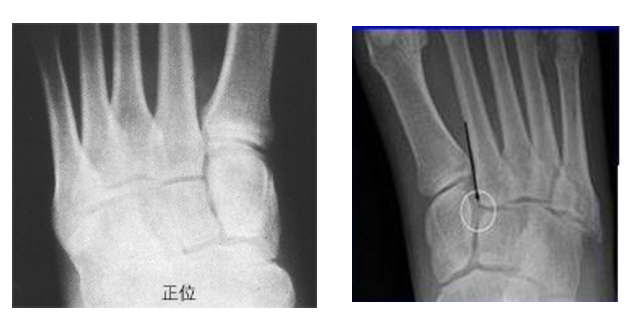

在足正位X线上,第1、2、3跖骨的内外侧缘分别和它相对应的楔骨的内外侧缘呈一直线排列;第一、二跖骨基底间隙和内中楔骨间隙相等。

30°斜位上:1、第四跖骨内侧缘和骰骨内侧缘连续成一条直线2、第三跖骨内侧缘和外侧楔骨内侧缘连续成一条直线3、第二、三跖骨基底间隙和内、中楔骨间隙相等。

侧位上,跖骨不超过相应楔骨背侧缘。从远端的跖骨经过跖跗关节到近端的跗骨,应该是一条不间断的连线

2005年Pearse等提出“ABC”的方法来阅读足部X 线片, 以减少中、前足的漏诊。 A ( alignment)检查跖骨与相应楔骨的对应线 B ( bone)检查每一块骨的轮廓 C ( congruity )检查整体一致吻合, 在正位片上观察内柱, 在斜位片上观察中、外柱。侧位片的常规检查可发现Lisfranc关节矢状面的半脱位及撕脱性骨折